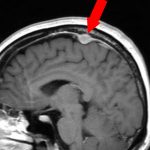

右傍矢状洞髄膜腫

頭蓋内腫瘍摘出術

No.’23_63 手術前1

No.’23_63 手術前2